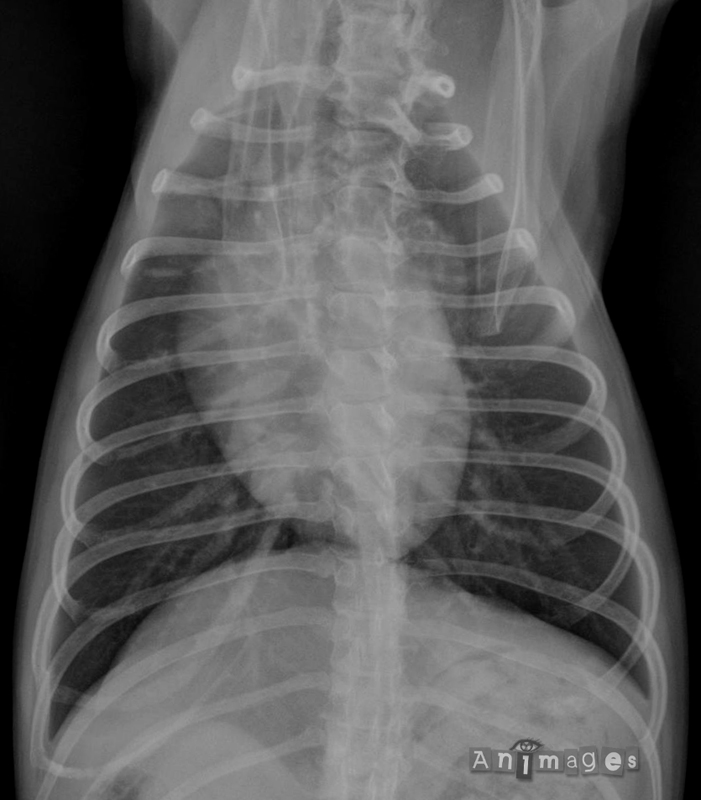

Thorax; ventrodorsale